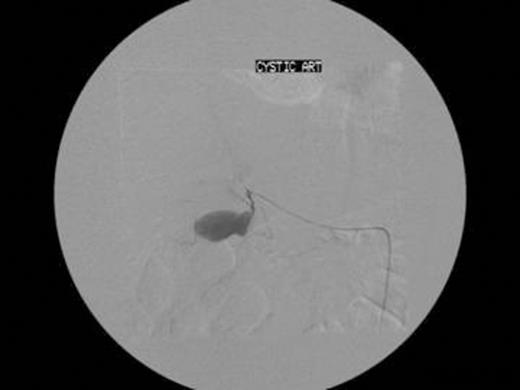

The next step was for embolisation of the CAP. A transfemoral approach was employed and a microcoil placed successfully in the cystic artery (Fig. 2). A right sub-hepatic drain was placed, which drained a total of 1130ml of dark inflammatory fluid, in the first 24 hours. The patient clinically improved over the next 7 days, his inflammatory markers normalised and the drain was removed when dry. The patient was discharged home and laparoscopic cholecystectomy was arranged electively.